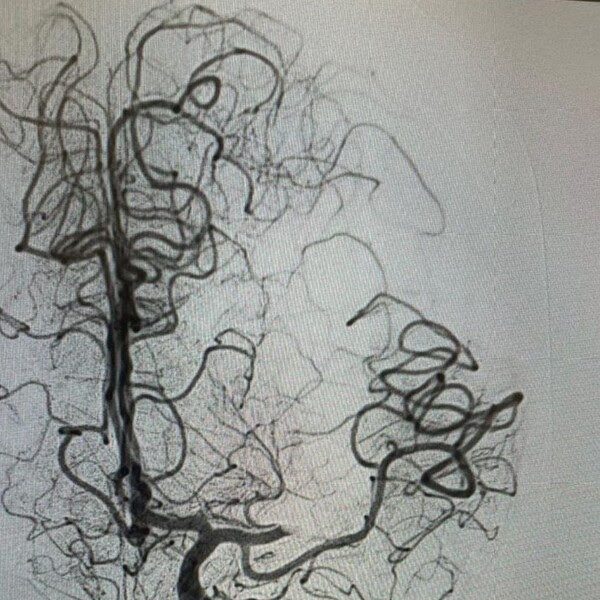

La paciente, quien tenía antecedentes de arterioesclerosis y problemas en las arterias carótidas, sufrió una pérdida súbita de movilidad en la mitad de su cuerpo, junto con problemas de habla y parálisis facial. Una resonancia magnética reveló la obstrucción de una arteria debido a un coágulo, lo que llevó a la intervención. Los médicos introdujeron catéteres desde la ingle hasta el cerebro para restablecer el flujo sanguíneo.

Gracias a este procedimiento, la paciente comenzó a experimentar una mejora en su circulación sanguínea hacia el cerebro. La recuperación de su lenguaje y movimiento se espera que sea gradual, con la ayuda de sesiones de fisioterapia, tratamiento farmacológico y cambios en su estilo de vida.